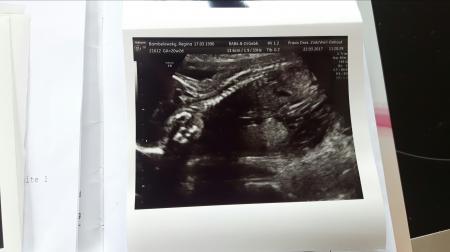

Hiiii ihr Süßen! Ich war heute zum Spezialisten zum organscreening! Es wurde super schöne 20 Minuten lang geschallt und Baby von Kopf bis Fuß genau angeschaut! Es ist alles super entwickelt und unauffällig! Niere, Herz, Lunge, Gehirn... einfach alles! Selbst an den Füßen konnten wir die Zehen zählen! Unser Würmchen ist einfach Zucker! Wir sind total verliebt! Ein Outing haben wir selbstverständlich auch bekommen! Wir verstärken, wie soll es auch anders sein, Team blau! In seiner ganzen männlichen Pracht hat er sich stolz gezeigt der kleine Lümmel! Wir sind überglücklich und freuen uns sehr! Unser Spatz hat super mitgemacht heute! ( Eigentlich sollte der Text voller Smileys sein, gehen nur leider nicht) Vielen Dank fürs Daumen drücken, ich drücke natürlich weiterhin für euch die Daumen!!!! Liebe Grüße Chrissy

Uuuuppsss Bild vergessen

Bild zu

Huhu dein kleiner liegt aber schön da. Meine Kleine lag heute wie ein Hase in der Fluchtstellung . Das einzige was super zu sehen ist, ist die Wirbelsäule. Lg Regina